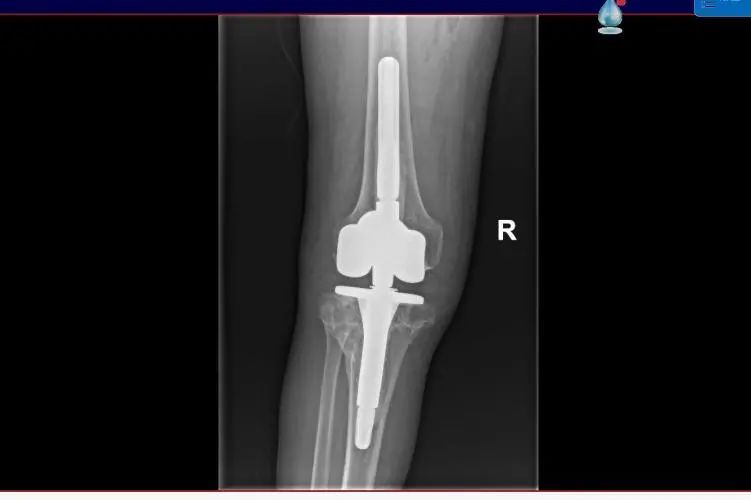

12日,手术顺利完成,尤大叔患者膝关节的运动功能恢复良好,手术后第一天就开始进行床上屈伸活动,第二天开始逐渐下地站立、行走。据了解,尤大叔将于11月16日出院。

▲术后影像

沈灏指出,人工膝关节置换手术是临床治疗膝关节疾病的常用手段,但膝关节表面置换假体通常适用于绝大多数的初次膝关节置换手术,对于部分严重畸形的膝关节病变及需要翻修的关节而言,普通表面型假体就显得力不从心,需要使用特殊设计的限制型假体来治疗?!靶铝聪プ魑拗菩约偬宓木渖杓?,为复杂手术中面临的严重骨缺损、韧带缺失等问题提供了简便的解决方案,使手术更安全、高效?!?/p>